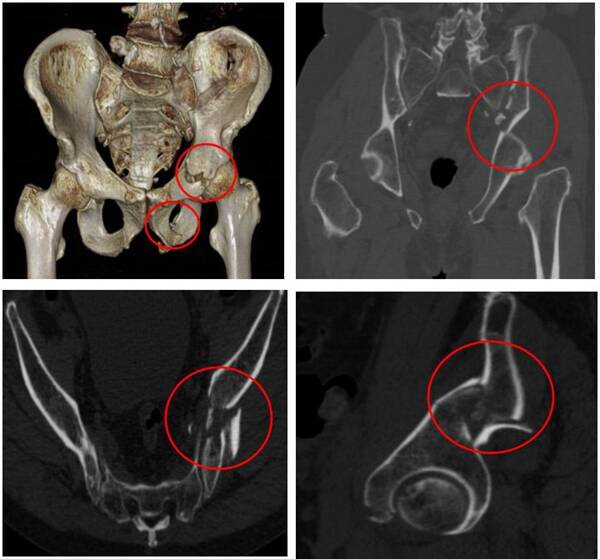

3D打印模型

副主任醫(yī)師丁祥、主治醫(yī)師孟慶禹立即與科室團(tuán)隊(duì)討論治療方式。對(duì)于骨盆骨折,傳統(tǒng)手術(shù)方法是需要將骨盆周?chē)蝗η虚_(kāi),創(chuàng)傷大、恢復(fù)慢,術(shù)中稍有不慎,患者就會(huì)面臨失血性休克、死亡的風(fēng)險(xiǎn)。考慮到蔣大爺年齡偏大、骨質(zhì)疏松、既往有高血壓及腦梗死個(gè)人史等情況,決定為蔣大爺行骨盆微創(chuàng)手術(shù)治療。

在骨科三病區(qū)主任阮傳江、副主任韓玉虎的指導(dǎo)下,麻醉科、手術(shù)室通力協(xié)助,創(chuàng)傷骨科結(jié)合術(shù)前3D打印技術(shù),為患者行“骨盆骨折閉合復(fù)位通道螺釘內(nèi)固定術(shù)”。該手術(shù)創(chuàng)傷小,術(shù)中出血少,術(shù)后恢復(fù)快,是真正意義上的骨盆骨折的微創(chuàng)治療。

通道螺釘手術(shù)就是用幾根長(zhǎng)度不同的螺釘將復(fù)位后的骨盆骨折穩(wěn)定固定,由于骨盆周?chē)笱芗吧窠?jīng)密布,失之毫厘差之千里。創(chuàng)傷骨科醫(yī)療組謹(jǐn)慎嚴(yán)密地完成了術(shù)前設(shè)計(jì),結(jié)合3D打印技術(shù),設(shè)計(jì)通道螺釘?shù)倪M(jìn)釘點(diǎn)及螺釘?shù)耐ǖ婪较?、長(zhǎng)度,術(shù)中通過(guò)骨盆入口位、出口位、骶骨側(cè)位、髂骨斜位、閉孔斜位等多角度術(shù)中XC臂機(jī)透視,精準(zhǔn)植入通道螺釘,避免了術(shù)中損傷環(huán)骨盆血管、神經(jīng)及螺釘穿出關(guān)節(jié)。